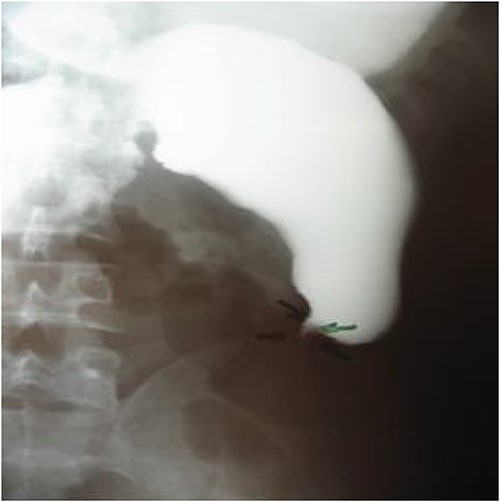

A 28-year-old male patient, with no notable medical history, had been experiencing epigastric abdominal pain for a year, followed by early postprandial vomiting without gastrointestinal transit disorders, in the context of unquantified progressive weight loss. Upon admission, the patient was in poor general condition, had no fever, with slightly pale conjunctivae. Abdominal examination revealed epigastric succussion splash with a downward dullness, but no hepatosplenomegaly. Lymph nodes were nonpalpable. The rest of the physical examination showed no particular findings. Laboratory tests showed hypokalemia at 2.96 meq/l and anemia with a hemoglobin level of 10.6 g/dl. Neutrophils and eosinophil counts were normal. Urgent esophagogastroduodenoscopy revealed significant gastric stasis hindering the examination, and an aspiration tube was placed, removing 1500 ml of fluid. After gastric emptying, the endoscopic examination was unremarkable except for a slightly congestive appearance of the antro-fundic mucosa, and systematic biopsies were performed. The histopathological examination showed interstitial antro-fundic lesions without specific or tumoral signs. Esophagogastric-duodenal transit imaging visualized a gastroduodenojejunal dilation upstream of a tight jejunal stenosis, suggestive of a highly probable malignant tumor process (Fig. 1). A stay in the intensive care unit to stabilize and monitor the hemodynamic status followed by surgical intervention was decided.

Esogastroduodenal transit showing gastroduodenal dilatation upstream of a tight jejunum stenosis.